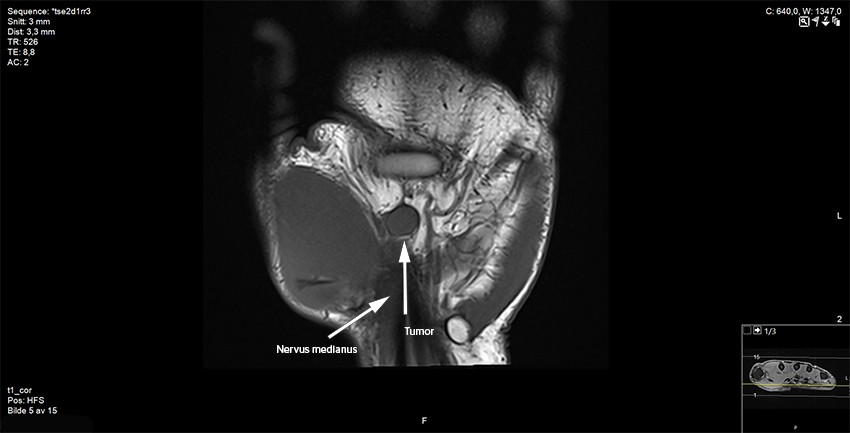

Pasienten ble deretter henvist til MR-undersøkelse ved privat klinikk og videre til ortopedisk avdeling ved regionsykehus. Etter MR-undersøkelsen beskrev radiologen en kontrastladende, velavgrenset bløtdelstumor like ved eller på nervus medianus ved utgangen av karpaltunnelen. Konklusjonen var at tumor var forenlig med et scwhannom, men at annen tumor ikke kunne utelukkes (figur 2 og 3).

Pasienten var plaget av kulen og ble tilbudt operasjon i narkose. MR-bildene ble forevist radiologer ved regionsykehuset. Arbeidsdiagnosen var et schwannom i relasjon til nervus medianus. Etter å ha spaltet karpalligamentet kom vi inn på tumor, som lå på medianusnerven der den forgrener seg utover i hånden. Tumor var ca. 10 × 10 mm og velavgrenset, og lot seg fridissekere fra nerven med unntak av den motoriske thenargrenen, som gikk tvers gjennom tumor og måtte reseseres. Nervegrenen lot seg sy uten behov for nervegraft. Makroskopisk syntes vi tumor liknet mest på et schwannom, men på grunn av innvekst i nerven var nevrofibrom en nærliggende differensialdiagnose. Vevspreparat ble sendt til histologisk analyse.

Pasienten ble umiddelbart informert om biopsisvaret og henvist til sarkomsenter. De preoperative MR-bildene ble gransket på ny av tumorradiologer. De konkluderte med at det var solid vaskularisert tumor langs nervus medianus og ikke noe typisk «target sign» eller «fascicular sign», som ofte ses ved benigne nerveskjedesvulster. Noen mer presis diagnose kunne ikke stilles basert på de preoperative MR-bildene. CT toraks, CT abdomen og ultralyd av glandler i aksillen viste ingen tegn til metastaser. Ny MR-undersøkelse av hånden viste ingen tumorrest. På grunn av tumors beliggenhet tett på stor nerve og sener ble ikke utvidet reseksjon anbefalt. Pasienten ble gitt postoperativ strålebehandling, 2 Gy × 30, for å minske risikoen for lokalt residiv. Ved siste kontroll hadde sårene etter strålebehandlingen tilhelet. Pasienten hadde ingen plager med nervesmerter og ingen nerveutfall.